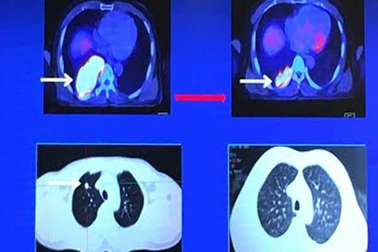

Bác sĩ sống tốt sau 5 năm ung thư phổi di căn khắp ngườiPhát hiện ung thư phổi ở giai đoạn muộn, tái phát nhiều lần, di căn cả vào xương, não nhưng gần 5 năm qua, PGS.TS Đỗ Quốc Hùng vẫn làm việc bình thường.

70% ca ung thư phổi phát hiện ở giai đoạn muộnDo những dấu hiệu đầu tiên của ung thư phổi không rõ ràng nên dễ bị bệnh nhân bỏ qua khiến hơn 70% trường hợp ung thư phổi chẩn đoán ở giai đoạn muộn (giai đoạn III, IV). Do đó, dù có nhiều bước tiến trong chẩn đoán và điều trị, tỉ lệ sống thêm 5 năm của bệnh nhân khá thấp.